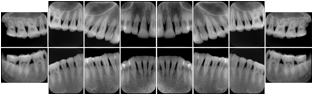

OO.1.2 Ophthalmology

1. A patient in rural Canada visits a general ophthalmologist and is found to have diabetic macular edema. The general ophthalmologist would like to discuss the case with a retina specialist before performing laser surgery. A fluorescein angiogram is done with multiple retinal images taken in a timed series after an intravenous injection. The images along with a Structured Display are shared via a Health Information Exchange with a retina specialist in Calgary, who opens them using his Ophthalmology EMR software and consults via phone with the general ophthalmologist. Both physicians view the images in the same layout so the retina specialist can provide accurate guidance for treating the patient.

2. A patient in rural Iowa visits his primary care physician for management of diabetes. Three non-mydriatic (patient's eyes are not dilated) photographs are taken of the back of each eye, and forwarded electronically along with a Structured Display to an ophthalmologist in Iowa City. The ophthalmologist reads the photos in an agreed upon layout so there is no mistake about what portion of which eye is being viewed. The ophthalmologist is able to tell the primary care physician that his patient does not need to come to Iowa City for face to face ophthalmologic care, but that there is a particular view of the left eye that should be photographed again in 6 months.

Ophthalmic Retinal Study Structured Display

Figure OO-3. Ophthalmic Retinal Study Structured Display

3. A patient in rural Minnesota experiences sudden vision loss and goes to a general ophthalmologist, who acquires OCT images and forwards them electronically along with a Structured Display to a retina specialist six travel hours away. The retina specialist is able to view the images in the standard layout that he is comfortable with, and to confirm that the patient has a choroidal neovascular membrane. He determines that is would be worthwhile for the patient to travel for treatment.

OCT Retinal Study with Cross Section and Navigation Structured Display

Figure OO-4. OCT Retinal Study with Cross Section and Navigation Structured Display